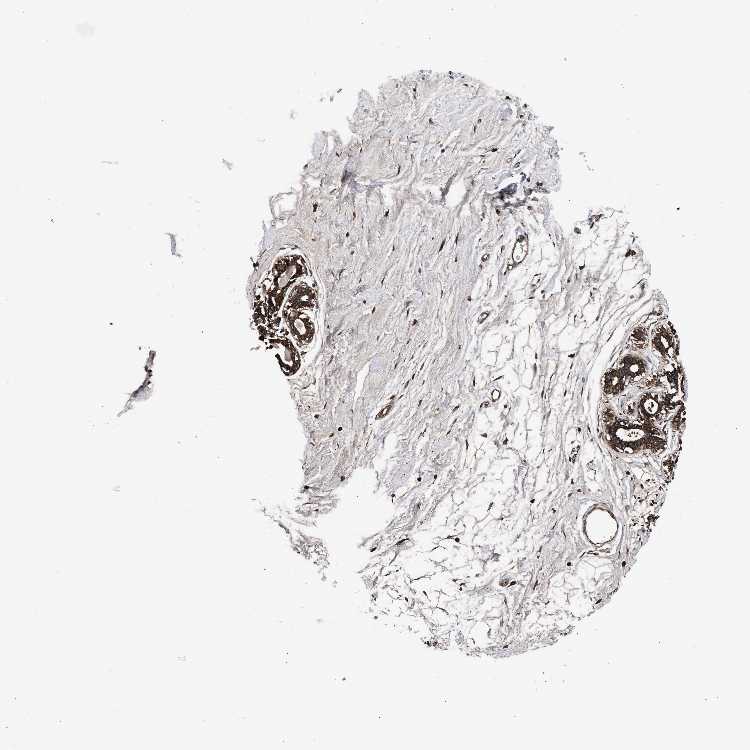

BREAST - Antibody stainingi

Antibody staining in the annotated cell types in the current human tissue is reported as not detected, low, medium, or high, based on conventional immunohistochemistry profiling in selected tissues. This score is based on the combination of the staining intensity and fraction of stained cells.

Each image is clickable and will lead to virtual microscopy that enables deeper exploration of all samples and also displays staining intensity scores, fraction scores and subcellular localization as well as patient and tissue information for each sample.

Antibody HPA021176Antibody HPA021177Antibody HPA027736

Adipocytes MediumMediumNot detected

Glandular cells HighHighNot detected

Myoepithelial cells HighMediumNot detected